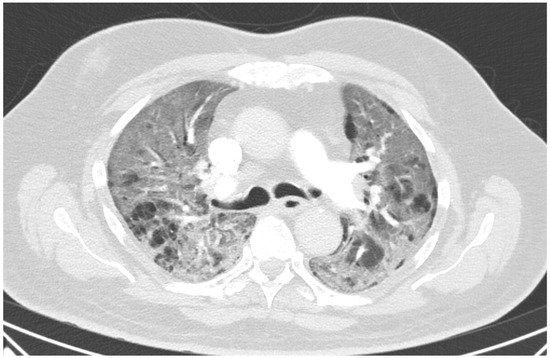

Figure 1. Lung CT on day 11 showing multifocal ground-glass opacities with crazy paving signs bilaterally.

Case Presentation

A 60 year old male smoker with a history of arterial hypertension and myocardial infarction developed typical COVID-19 symptoms in April 2021—cough, exertional dyspnoea, chest tightness, and fever. Developing prior to the widespread availability of antiCOVID-19 vaccines, he was unvaccinated. Four days after the onset of symptoms, he was admitted to the Pulmonary Department of the University Hospital Brno due to the worsening dyspnoea. He tested positive for SARS-CoV-2. The exact viral variant was not identified. The predominant variant in the Czech population was B.1.1.7 (Alpha) at that time. His initial chest X-ray revealed diffuse lung infiltrates, especially in the right upper-middle quadrant. Despite receiving standard treatment with remdesivir for five days, corticosteroids (methylprednisolone 80 mg intravenously per day), and a prophylactic dose of low-molecular-weight heparin (LMWH), his dyspnoea worsened. Hence, supplemental oxygen and antibiotics (i.e., clarithromycin 500 mg IV BID and ceftriaxone 2 g IV BID for 5 days) were administered. Due to the progressively increasing levels of D-Dimers in laboratory tests, CT angiography was performed, showing typical findings consistent with COVID-19 pneumonia of diffuse lung parenchyma involvement without any signs of pulmonary embolism (Figure 1). The patient’s oxygen was gradually increased to achieve a peripheral blood saturation of >90%. On day 11, the patient was transferred to the ICU after his saturation dropped to 50–60% despite an oxygen flow via face mask of approximately 15 litres per minute. High-flow oxygen therapy (HFOT) with awake prone positioning was commenced, and corticosteroids were switched from methylprednisolone 80 mg to dexamethasone 6 mg IV per day. Despite ten days of corticosteroid administration, the patient’s clinical condition began to deteriorate significantly, and his hypoxaemia worsened. On day 12, he was intubated and placed on invasive ventilation with aggressive parameters (positive end-expiratory pressure: 12 cm H2O; fraction of oxygen: 80%). Bronchoalveolar lavage (BAL) was performed with the PCR testing showing more than 2 million copies of SARS-CoV-2 per millilitre (a significant number); no fungal DNA was detected at this time. As the patient became anuric, daily dialysis treatment commenced on day 13. Ventilator-associated pneumonia (VAP) caused by Klebsiella pneumoniae producing extended-spectrum beta-lactamase (ESBL) was confirmed by BAL fluid cultivation, and meropenem 2 g per day in continuous infusion was started. Serum levels of cardiac markers were elevated (troponin T: 67 ng/L; NT pro Brain Natriuretic Peptide (NTproBNP): 3892 ng/L), indicating advancing myocardial injury. Norepinephrine infusion was needed to achieve adequate blood pressure. The capillary refill time was prolonged over 2 s, consistent with circulatory dysfunction. A day later, the patient developed atrial fibrillation and hemodynamic instability with doses of norepinephrine up to 0.5 µg/kg/min. On day 16, a tracheostomy was performed, while the ventilation remained fully controlled with a P/F (PaO2/inspiration fraction of O2) index below 150. Two days later, the progression of circulatory dysfunction became apparent, accompanied by an elevation of inflammatory markers. Follow-up BAL was performed, empirical vancomycin was added on day 19, and doses were adjusted respecting dialysis procedures. Abdominal ultrasound revealed no clear site of a new infection. Blood cultures were negative, and BAL showed more than 3 million copies of SARS-CoV-2 and 1200 copies of Cryptococcus neoformans per millilitre/BAL. Serum panfungal antigen ((1,3)-β-glucan D) and serum cryptococcal antigen (i.e., glucuronoxylomannan) levels were negative. Over the next four days, organ dysfunction slightly improved; therefore, the patient was slowly weaned-off sedation, and the mode of ventilation was switched to pressure support. On day 21, vancomycin was switched to linezolid 600 mg IV BID. On day 22, a follow-up BAL was performed. PCR showed borderline positivity for Cryptococcus neoformans (300 copies per millilitre), and serum positivity for cryptococcal antigen was detected. Combined antifungal therapy with liposomal amphotericin B (Abelcet) 500 mg IV per day and fluconazole 800 mg IV per day was commenced. Blood cultures were negative for bacteria and fungi. Cerebrospinal fluid analysis, including PCR, ruled out CNS dissemination. On day 24, the patient’s circulatory instability progressed rapidly with no response to vasopressors and inotropes, which led to a subsequent cardiac arrest followed by unsuccessful cardiopulmonary resuscitation (CPR). Multiorgan dysfunction caused by COVID-19 infection and cryptococcal pneumonia was stated as the primary cause of death from a clinician’s perspective. The most significant feature during the histopathological examination was the severe diffuse alveolar damage (DAD) (Figure 2), specifically its exudative/proliferative stage, due to the prolonged period of COVID-19 pneumonia. In addition, a considerable number of dispersed intra-alveolar microorganisms, with a thick mucus capsule, were found in the lung parenchyma (Figure 3). These microorganisms (variably sized: approximately 7–20 μm) stained with both Alcian blue (Figure 4) and Giemsa (Figure 5). There was only a very subtle inflammatory reaction in the surrounding tissue, mostly lymphocytic. A post-mortem lung smear was microbiologically tested and returned positive for Cryptococcus neoformans. Thus, we consider secondary lung cryptococcosis as proven. Respiratory failure as a result of DAD was the immediate cause of death of the patient.